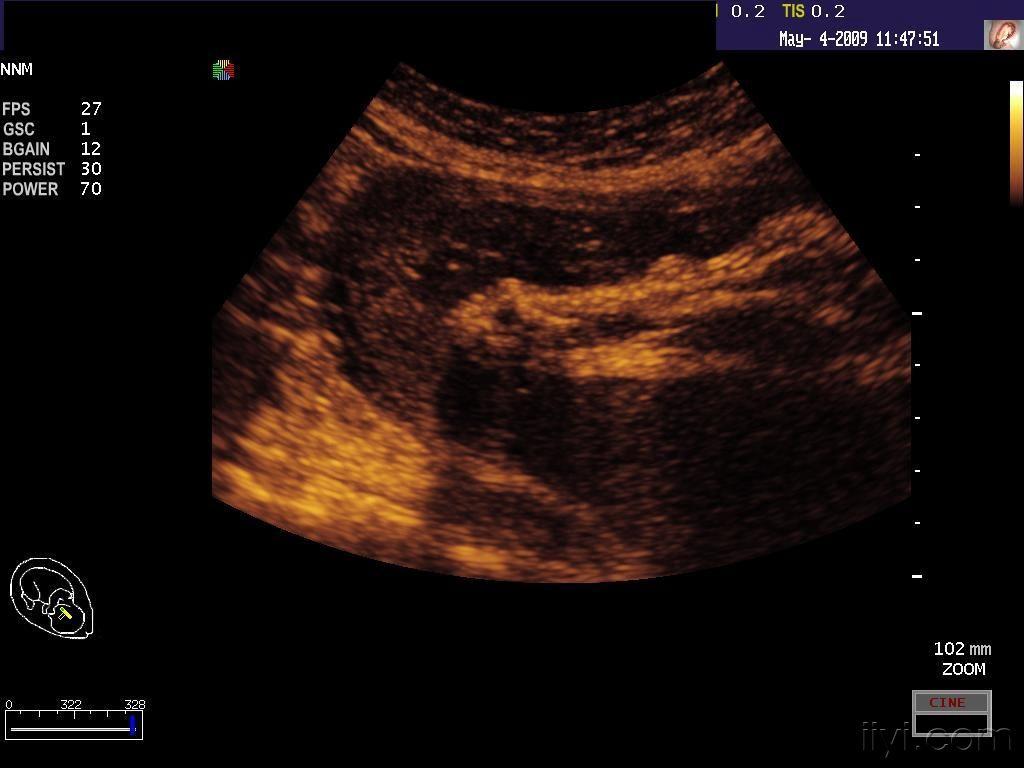

这是柠檬形胎头吗?附三维彩超报告

这个是柠檬头吗,属于畸形吗

这个是柠檬头吗属于畸形吗

"柠檬头"

胎儿头颅呈典型的"柠檬头"!胎儿的畸形是否是甲状